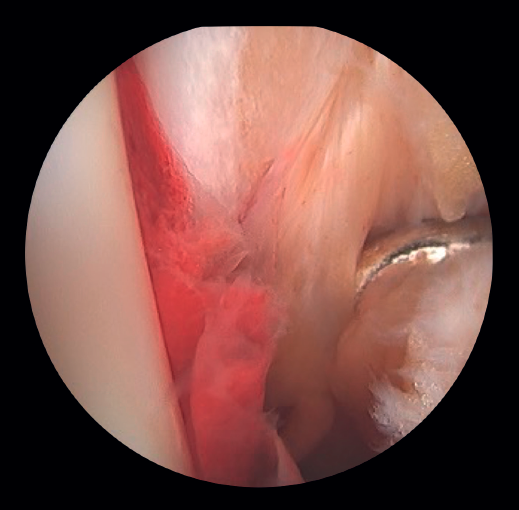

- Diagnóstico de inestabilidad sindesmal: la artroscopia permite la evaluación de la integridad de la sindesmosis y del ECM sobre la radiografía y la TC, sobre todo en la clasificación de las fracturas SER II y IV. Se ha demostrado que la evaluación radiográfica no siempre predice la lesión sindesmal. Además, la artroscopia permite asegurar una reducción anatómica de esta. Takao encontró que el 87% (33/38) de los tobillos con fractura tenían lesiones de la sindesmosis detectadas por artroscopia(20).

La artroscopia permite la visión directa de la sindesmosis y, además, permite su evaluación dinámica(22,21).

- Nos permite diferenciar entre fracturas SER II (en las que no debería existir lesión sindesmal) y fracturas SER IV, en las que sí hay afectación de la sindesmosis, pudiendo estabilizarla(5,23).

- Puede evitar la falsa impresión de un espacio articular medial ensanchado en la fluoroscopia debido a anomalías congénitas.

- Poder visualizar la incisura maleolar junto con el control radioscópico nos permite asegurar un correcto posicionamiento del peroné en la incisura fibularis, sobre todo en las lesiones inestables en las que existe riesgo de mala reducción por acortamiento o rotación del peronéa(5,24).

- Evitar la hipercorrección de la sindesmosis, que es muy artrogénica(5,24) (Figura 6).

Figura 6. A: lesión de sindesmosis; B: control de la reducción para evitar la sobrecorrección; C: control intraoperatorio de la correcta reducción del peroné en la incisura.